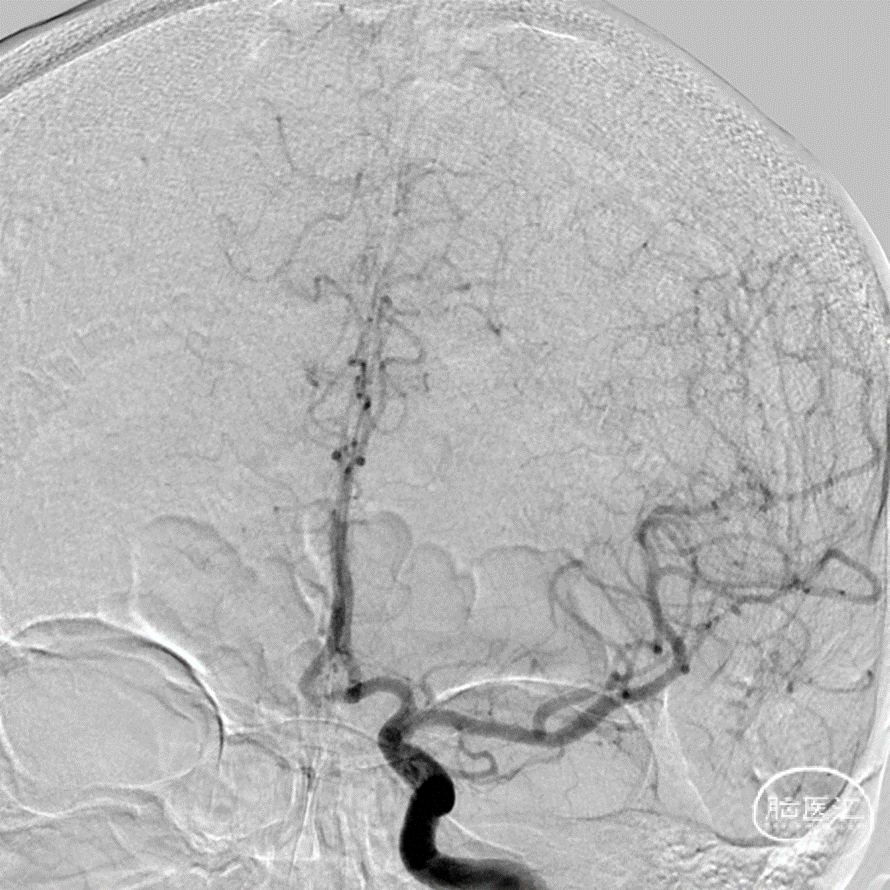

正位造影

DSA三维重建

DSA:数值测量

脉络膜前动脉动脉瘤和真性脉络膜前动脉动脉瘤的鉴别,后者的位置距离脉络膜前动脉和颈内动脉的连接处有一段距离